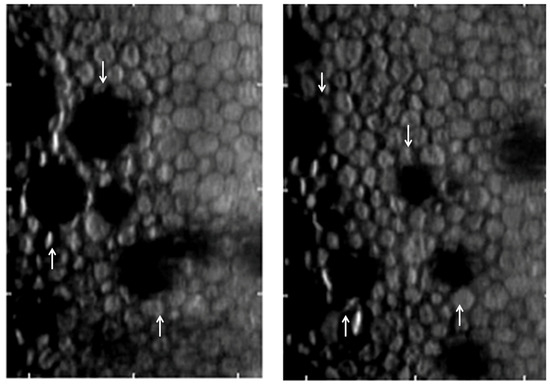

5. In Vivo Confocal Microscopy (IVCM)

- Mustonen, R.K.; McDonald, M.B.; Srivannaboon, S.; Tan, A.L.; Doubrava, M.W.; Kim, C.K. In vivo confocal microscopy of Fuchs’ endothelial dystrophy. Cornea 1998, 17, 493–503. [Google Scholar] [CrossRef] [PubMed]

- Amin, S.R.; Baratz, K.H.; McLaren, J.W.; Patel, S.V. Corneal abnormalities early in the course of Fuchs’ endothelial dystrophy. Ophthalmology 2014, 121, 2325–2333. [Google Scholar] [CrossRef]

- Schrems-Hoesl, L.M.; Schrems, W.A.; Cruzat, A.; Shahatit, B.M.; Bayhan, H.A.; Jurkunas, U.V.; Hamrah, P. Cellular and subbasal nerve alterations in early stage Fuchs’ endothelial corneal dystrophy: An in vivo confocal microscopy study. Eye 2013, 27, 42–49. [Google Scholar] [CrossRef]

- Ong Tone, S.; Bruha, M.J.; Böhm, M.; Prescott, C.; Jurkunas, U. Regional variability in corneal endothelial cell density between guttae and non-guttae areas in Fuchs endothelial corneal dystrophy. Can. J. Ophthalmol. 2019, 54, 570–576. [Google Scholar] [CrossRef] [PubMed]

- Syed, Z.A.; Tran, J.A.; Jurkunas, U.V. Peripheral Endothelial Cell Count Is a Predictor of Disease Severity in Advanced Fuchs Endothelial Corneal Dystrophy. Cornea 2017, 36, 1166–1171. [Google Scholar] [CrossRef] [PubMed]

- Aggarwal, S.; Cavalcanti, B.M.; Regali, L.; Cruzat, A.; Trinidad, M.; Williams, C.; Jurkunas, U.V.; Hamrah, P. In Vivo Confocal Microscopy Shows Alterations in Nerve Density and Dendritiform Cell Density in Fuchs’ Endothelial Corneal Dystrophy. Am. J. Ophthalmol. 2018, 196, 136–144. [Google Scholar] [CrossRef]

- Bucher, F.; Adler, W.; Lehmann, H.C.; Hos, D.; Steven, P.; Cursiefen, C.; Heindl, L.M. Corneal nerve alterations in different stages of Fuchs’ endothelial corneal dystrophy: An in vivo confocal microscopy study. Graefe’s Arch. Clin. Exp. Ophthalmol. 2014, 252, 1119–1126. [Google Scholar] [CrossRef] [PubMed]